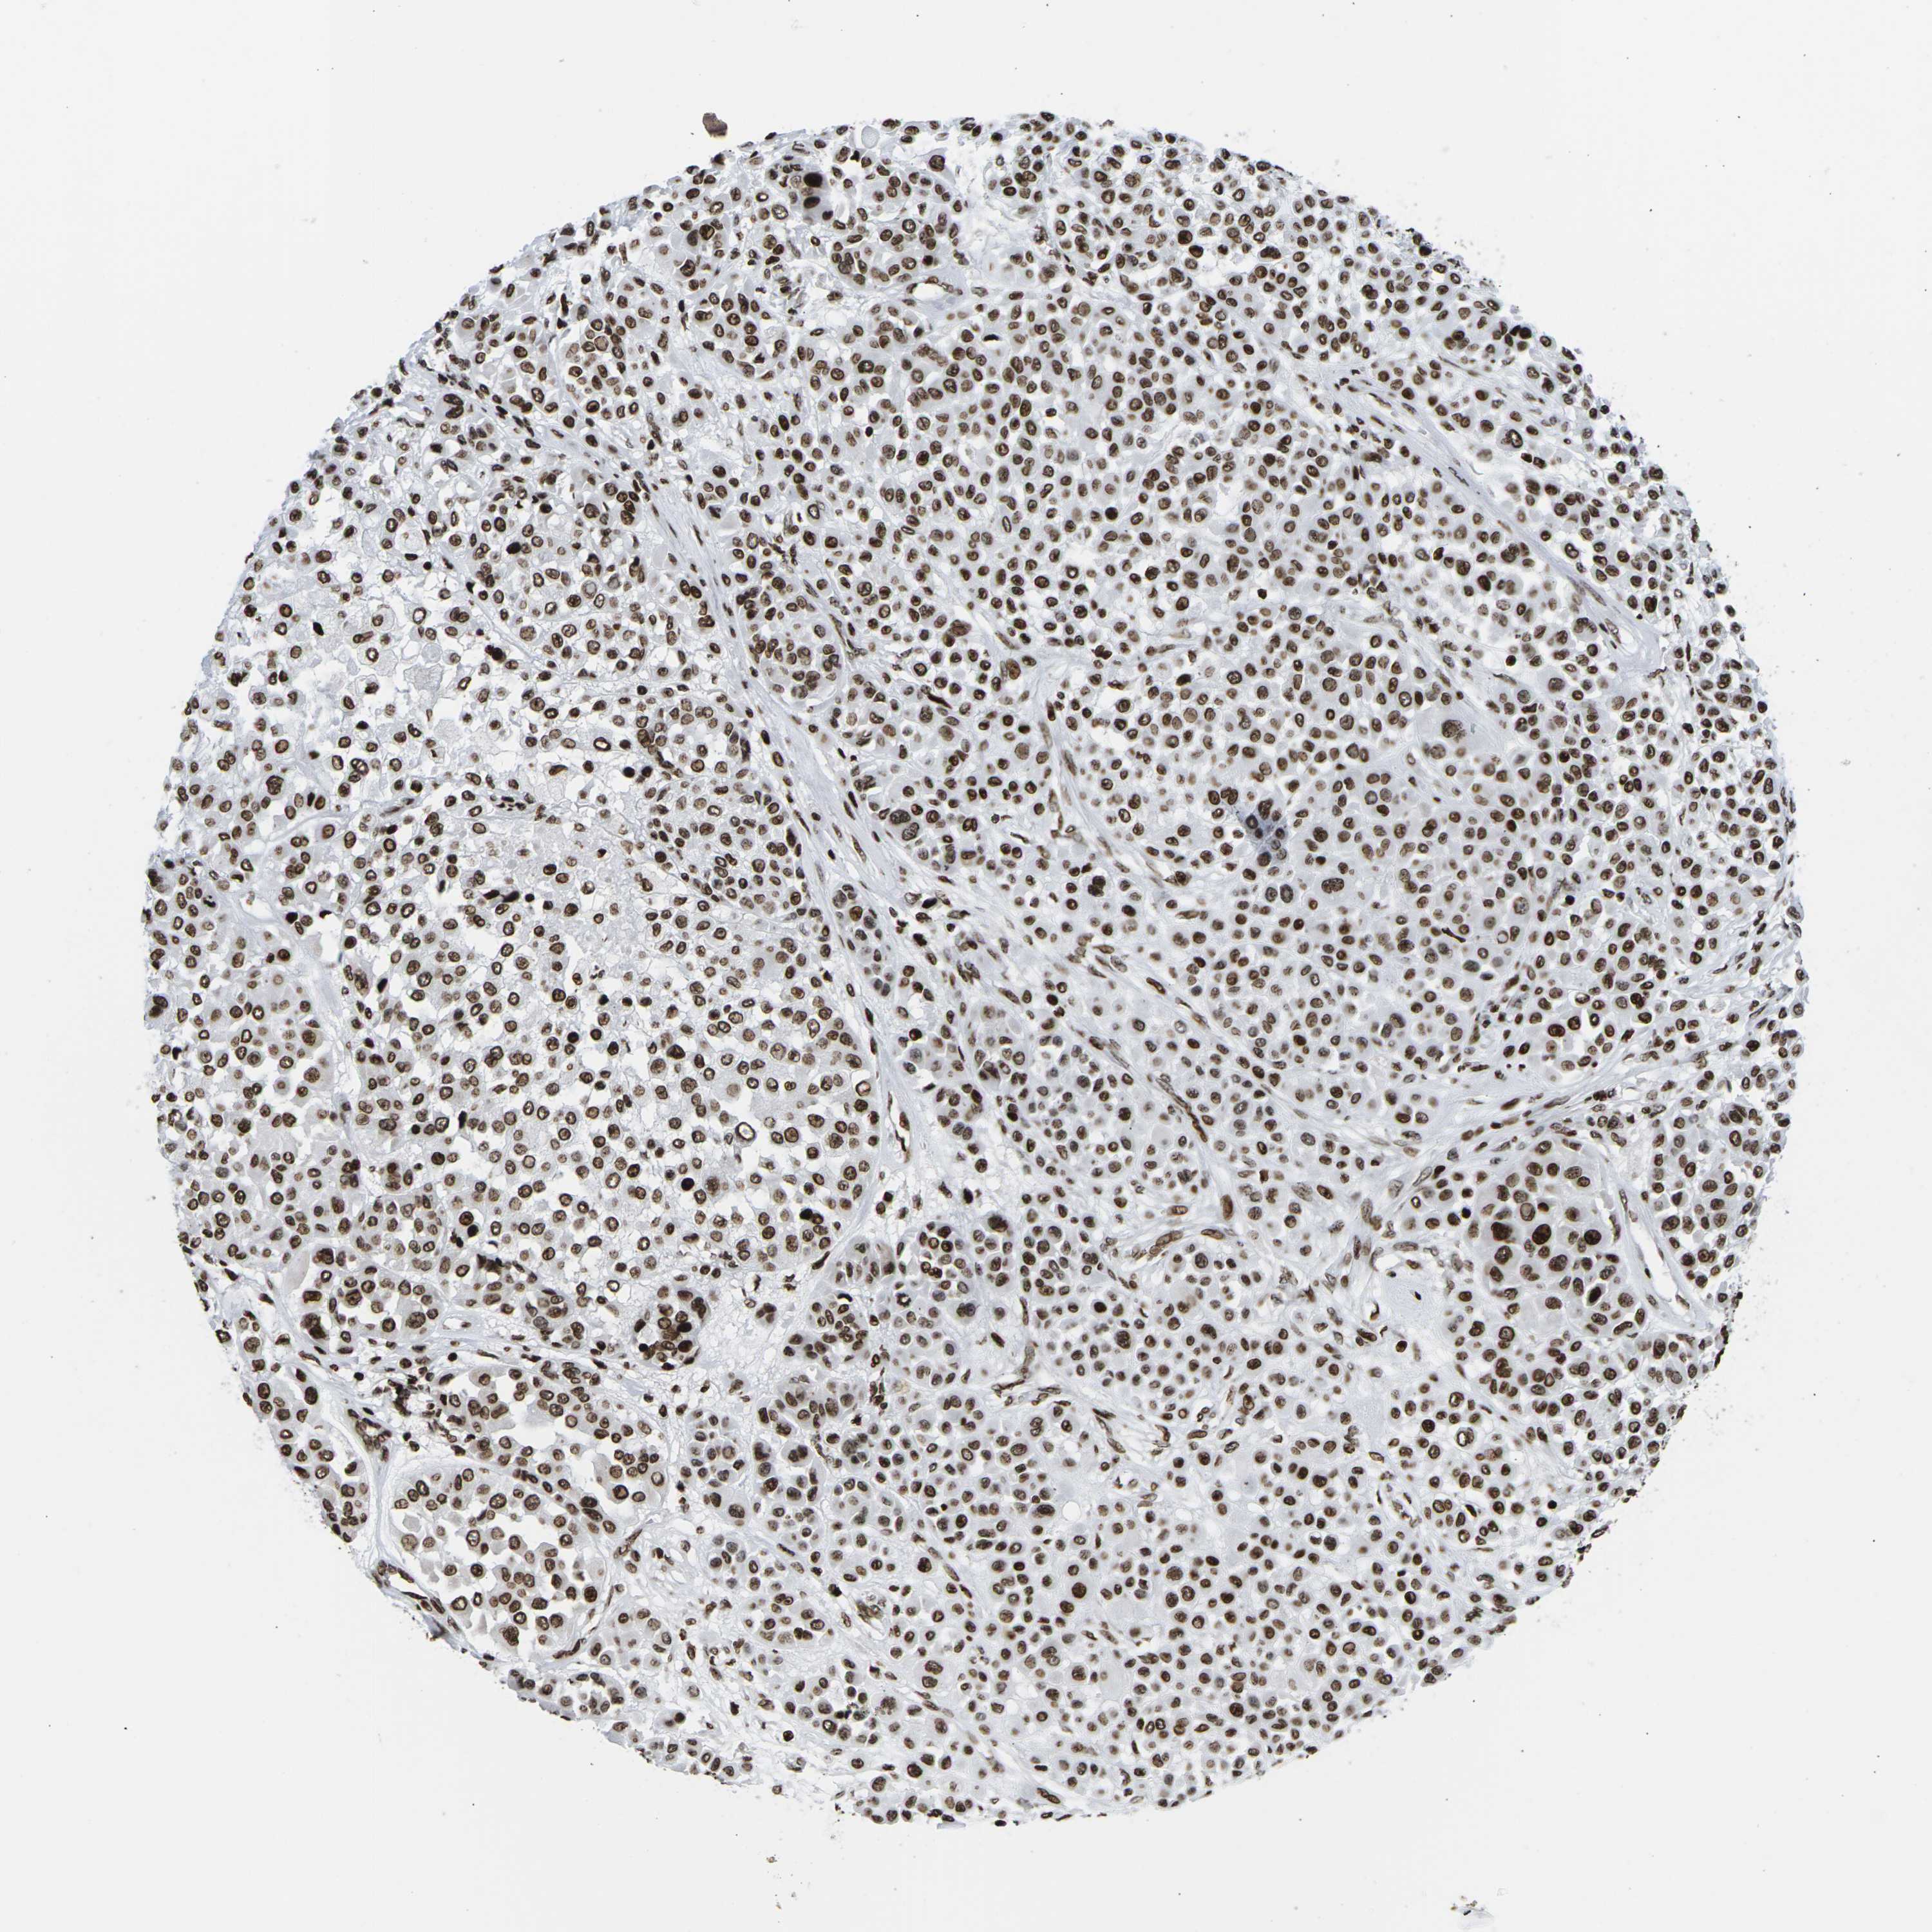

MELANOMA - Protein expressioni

A mouse-over function shows sample information and annotation data. Click on an image to view it in a full screen mode. Samples can be filtered based on level of antibody staining by selecting one or several of the following categories: high, medium, low and not detected. The assay and annotation is described here.

Note that samples used for immunohistochemistry by the Human Protein Atlas do not correspond to samples in the TCGA dataset.

Antibody stainingi

Antibody staining in the annotated cell types in the current human tissue is reported as not detected, low, medium, or high, based on conventional immunohistochemistry profiling in selected tissues. This score is based on the combination of the staining intensity and fraction of stained cells.

Each image is clickable and will lead to virtual microscopy that enables deeper exploration of all samples and also displays staining intensity scores, fraction scores and subcellular localization as well as patient and tissue information for each sample.

Antibody HPA055907

Antibody CAB011506

Staining

High

Medium

Low

Not detected

Intensity

Strong

Moderate

Weak

Negative

Quantity

>75%

75%-25%

<25%

None

Location

Nuclear

Cytoplasmic/membranous

Cytoplasmic/membranous,nuclear

Malignant melanoma, NOS

Malignant melanoma, Metastatic site